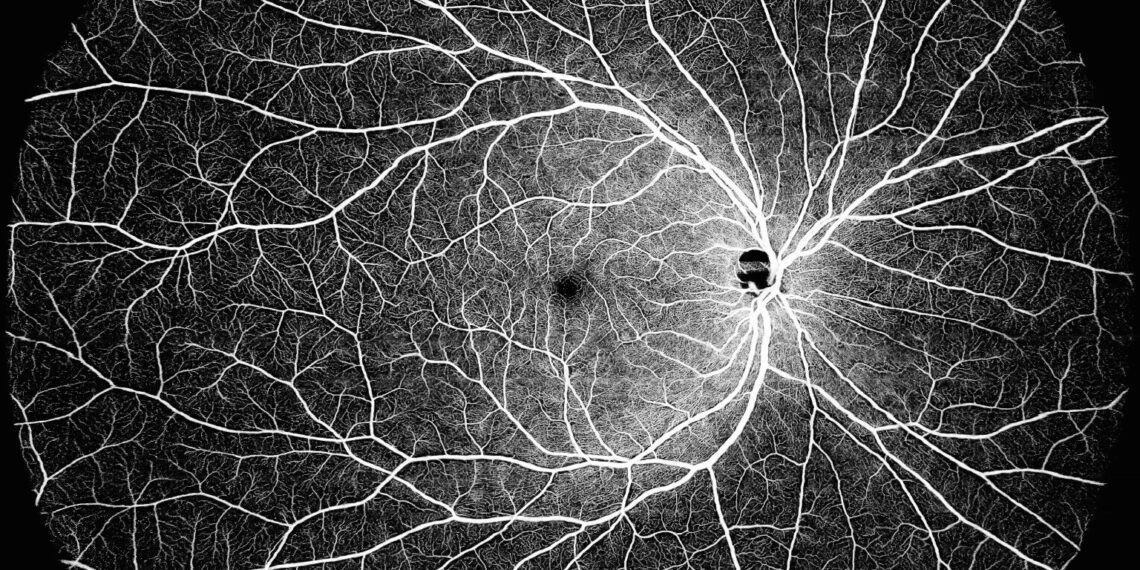

DREAM OCT is able to cover an ultrawide field single scan which delivers a 130° OCTA image. DREAM OCT™ swept-source 12 mm super-depth scanning allows superior imaging of the choroid and retina, and a large portion of the vitreous space. The super-depth anterior scanning capabilities achieves 16.2 mm (in air), allowing for the complete anterior segment from the cornea to the anterior part of the vitreous to be scanned in only one scan. The longer wavelength allows for superior penetration through opacities in either lens or vitreous.

Using ultra-wide swept-source technology, DREAM OCT was developed to address the needs of retina specialists, comprehensive ophthalmologists and their patients with highly-detailed imaging capabilities for improved care and results. Currently, more than 160 peer-reviewed papers have utilized findings from DREAM OCT devices.